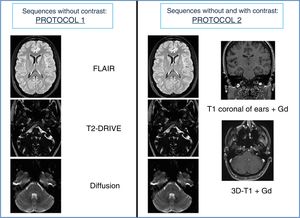

Sequence reading without IVC was called “protocol 1”, and sequences without and with IVC, “protocol 2” (Fig. 2).